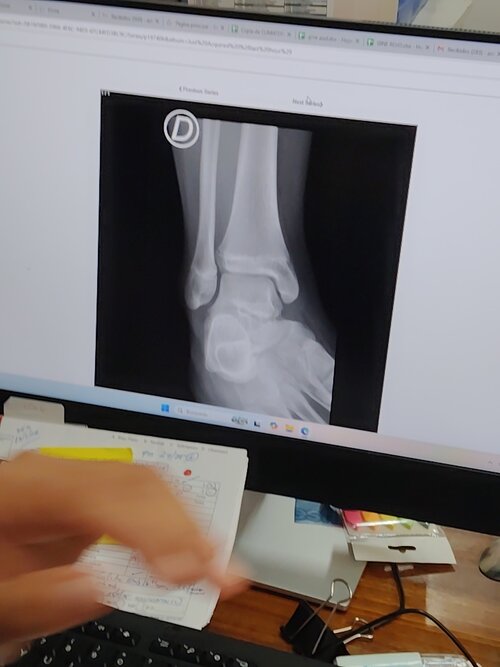

I had x-rays taken of my hand and leg, my cartilages are about to close, my cartilage age is 17 years, 163.5, 5'4 they didn't tell me anything good about this, my father is 174..